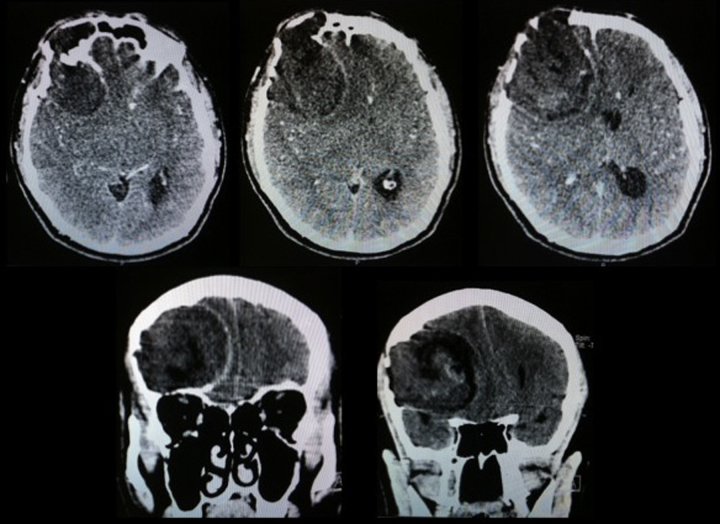

Fig. 4.

Simple skull tomography images, where lesion with important extra-axial intracranial mass effect is observed, with significant bone erosion with heterogeneous content.

Fig. 6.

Postoperative tomography images where the resolution of the mass effect that produced the lesion (a, b) is observed; also the bone defect that was observed (c) and subsequent cranioplasty images with methyl methacrylate (d, e) are observed.